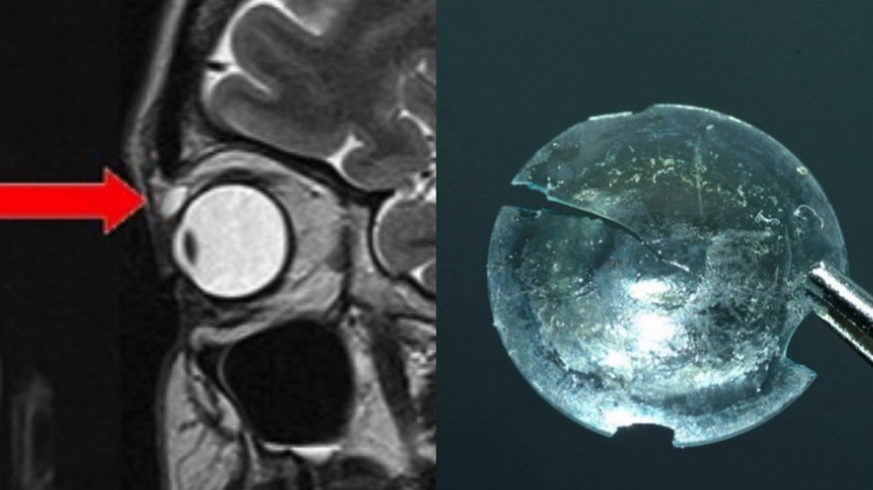

Grossbritannien Frau Hatte Kontaktlinse 28 Jahre Im Auge Der Spiegel

Arzte Entdecken 28 Jahre Alte Linse Im Auge Einer Patientin Watson

Kontaktlinse Im Auge Frau Lebt Unbemerkt 28 Jahre Mit Fremdkorper Stern De